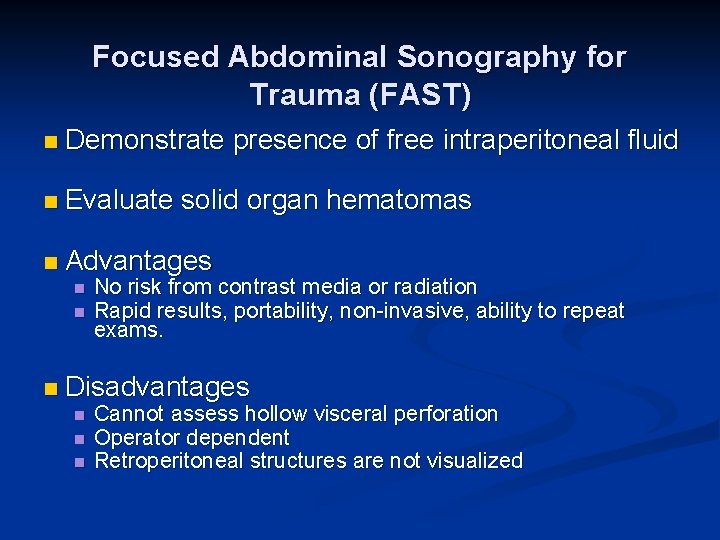

Focused Abdominal Sonography for Trauma (FAST) n Demonstrate presence of free intraperitoneal fluid n Evaluate solid organ hematomas n Advantages n n No risk from contrast media or radiation Rapid results, portability, non-invasive, ability to repeat exams. n Disadvantages n n n Cannot assess hollow visceral perforation Operator dependent Retroperitoneal structures are not visualized